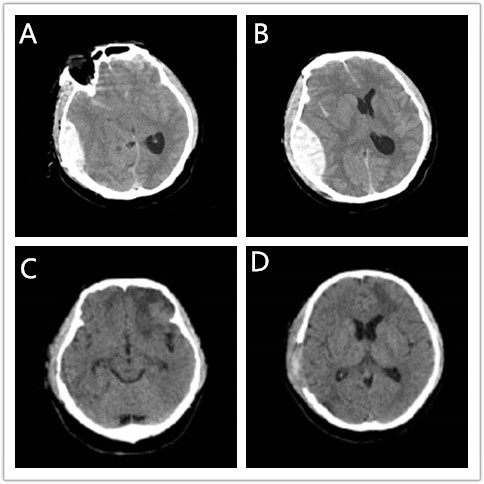

图A、B为术前颅脑CT:右侧颞部急性硬脑膜外血肿,侧脑室受压,中线结构移位。

图C、D为术后颅脑CT:硬膜外血肿清除完全,脑室受压解除,中线结构回归。